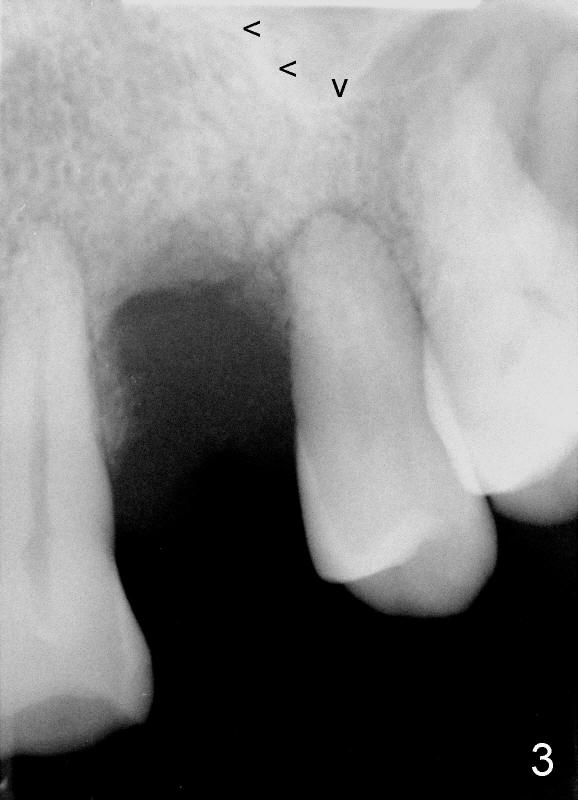

Dear Dr. Borgner: This Friday I may try D implant in a 50-year-old perio patient in #12 (Fig.1 *, Fig.2 is magnification of Fig.1 with sinus floor pointed by arrowheads), which was extracted ~ 1 month ago. PAs were taken yesterday (Fig.3). The socket must be partially empty. Can we start with RT2 or D1 spreader before using D2 one? #15 appears to be unnecessary. Tuesday, June 25, 2013 6:40 AM

Dr Wei, This is exactly what we spoke about in the class. 1- You can go right to the D2 channel former turned 90 degrees (Fig.4: design of D2 implant turned 90 degree). 2- Engage all of the apical bone you can without entering the sinus. 3- Do not remove any bone with a bur in order to not remove any remaining interseptal bone ! 4- Place a D2 implant as directed previously. This should work perfectly if you follow these steps. Dr Borgner Thursday, June 27, 2013 2:32 PM

Dear Drs. Dunson and Borgner: Thank you for support. Fig.5 and 6 taken immediately prior to surgery show that the healing socket is elliptical (arrowhead). After D1 and D2 channel formers, D2 thin socket former is tapped in (Fig.7). The osteotomy needs to be redirected as shown by the black line. D2 implant is being inserted with Synthograft applied to the 1st two threads (Fig.8) and is in place (Fig.9,10). But the implant is not as stable as expected. There is a gap mesial to the implant (Fig.10 arrowhead), which is most likely created by re-directing the osteotomy with channel and socket formers.